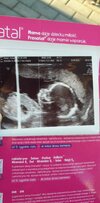

Mam termin na 17 lutego 🙂 moje pytanko do Was, czy z któraś ma podobne zdjęcie USG z około 17 tyg i okazało się, że jednak będzie dziewczynka 😜 czy to mogą być aż tak opuchnięte wargi sromowe? 🤔 wiadomo, że najważniejsze, żeby dziecioszek był zdrowy 🤞🏽 Ale bardzo nastawiłam się na dziewczynkę nie wiem czemu i jeszcze gdzieś z tylu głowy mam nadzieje, że z tego koleżki zrobi się koleżanka 🤣

Ja mam bardzo podobne zdjęcie. W 15 tygodniu powiedziano mi, że syn. Na kolejnej wizycie w 18 tyg potwierdzono 💙

Hej dziewczyny dawno mnie nie było ale pochwalimy się bedzie córka potwierdzone dzisiaj 19+5 tc termin na 19.02 ❤😍😊 273g szczęścia rośniemy 🥳👶

• a17d6e25-519a-4ad7-b9cc-b05141254da6.jpg

a17d6e25-519a-4ad7-b9cc-b05141254da6.jpg

46,1 KB · Wyświetleń: 144